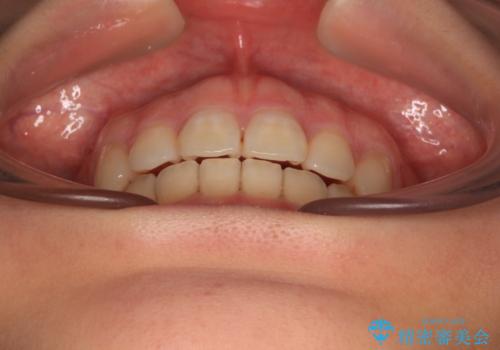

- 口元の突出感を気にして来院された患者様です。

口元を積極的に引っ込めるために、上下左右の第一小臼歯を4本抜歯することとし、ワイヤー装置による矯正治療を行うこととしました。

上下前歯がくちばしのように突出していましたが、抜歯矯正により口元が引っ込み、唇が閉じやすくなり、鼻の下の膨れた感じも解消されました。